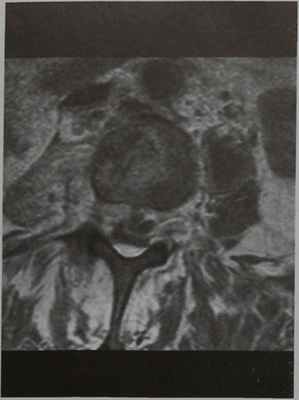

МРТ позвонка LIII (горизонтальная проекция, Т1 -взвешенное изображение с подавлением сигнала от жировой ткани и контрастированием). Псоас-абсцесс и эпидуральный абсцесс.